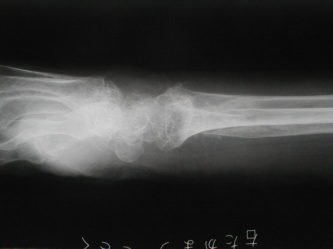

右前腕骨骨折

負傷日時 平成13年11月26日

自宅寝室からトイレに行きしなに、廊下で転倒した際に手をつき負傷

受傷時撮影1 受傷時撮影2